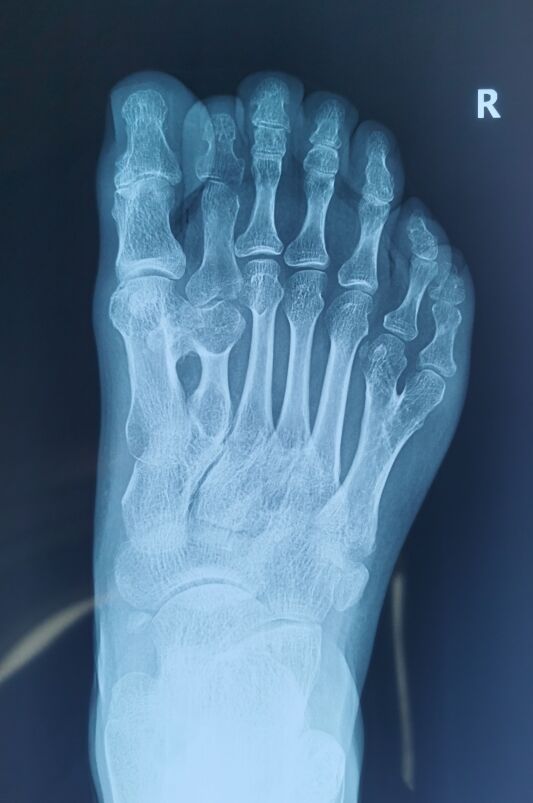

多趾畸形成人矫形

微信截图_20230928225120.png

微信截图_20230928225142.png

微信截图_20230928225207.png